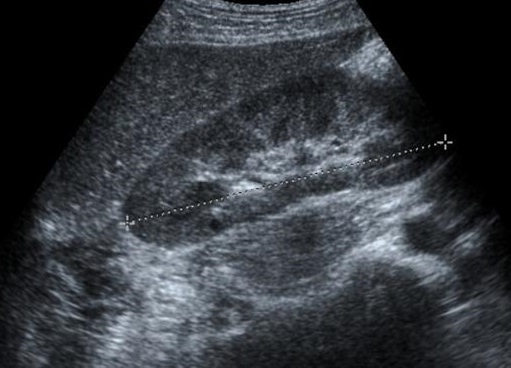

Image echographique de la

cirrhose du foie au debut

. Foie est en hypoechogene a bord irregulier , veine porte

est dilate |